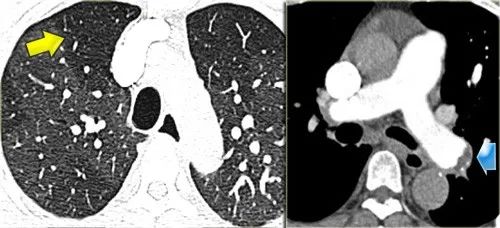

下图2例GGO,左侧无纤维化,可治疗;右侧伴牵引性支气管扩张,提示纤维化,不可治愈。

下图患者,GGO呈马赛克分布。

这里的线索是GGO区域肺动脉(箭头)的增大。

GGO的出现是由于慢性血栓栓塞性疾病导致少血肺旁的高灌注所致。

下图,另一位病人的GGO呈马赛克分布。

再一次,GGO的出现是由于慢性血栓栓塞病造成的肺过度灌注。

附壁栓子和血管内间隔是部分再通的慢性血栓栓子的典型表现。